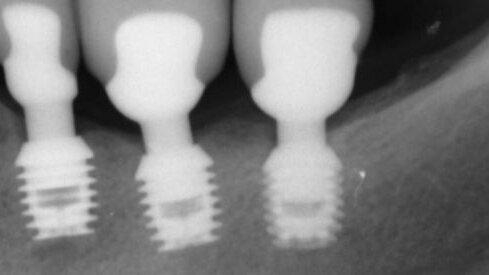

Roma, Italia: uno studio ha scoperto che gli impianti corti sono un’opzione di successo nei trattamenti a breve termine per le procedure ricostruttive in situazioni cliniche di limitata altezza verticale dell’osso. I ricercatori dell’Università di Roma hanno valutato in maniera sistematica gli studi clinici di impianti inferiori a 10 mm di lunghezza per determinare il successo di protesi supportate da impianti corti nei casi di mandibola atrofica.

Infine, i ricercatori hanno selezionato e analizzato due studi randomizzati e controllati e 14 studi osservazionali, indagando 6.193 impianti corti da 3.848 partecipanti. Hanno trovato una percentuale cumulativa di sopravvivenza del 99,1%, una percentuale di successo biologico del 98,8% e una percentuale di successo biomeccanico del 99,9%. Una più alta percentuale di sopravvivenza complessivo è stata segnalata per gli impianti con superficie ruvida.

I ricercatori hanno concluso che l’applicazione di protesi supportate da impianti corti nei pazienti con creste alveolari atrofiche sembra essere un’opzione di trattamento a breve termine di successo. Tuttavia, ritengono che siano necessari ulteriori studi scientifici per accertare se questa possa essere anche una valida opzione a lungo termine.

Negli ultimi anni sempre più autori si sono interessati all’utilizzo degli impianti corti, cioè di impianti di lunghezza pari o ...